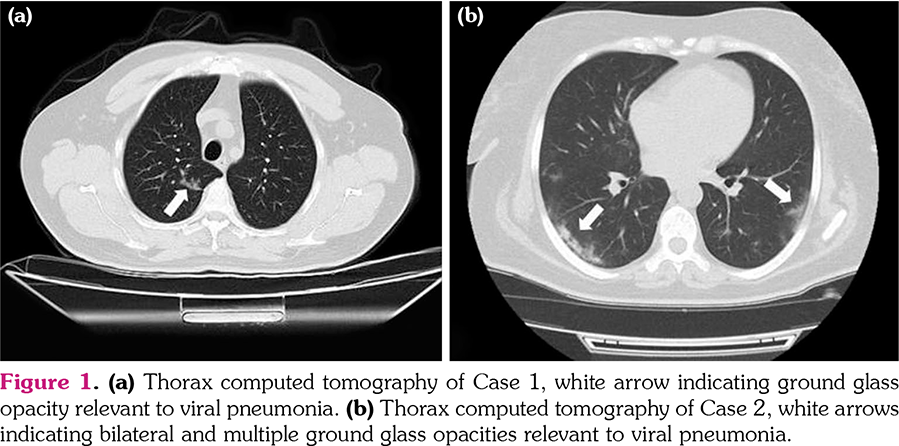

Case 2- A 44-year-old male patient with AS applied to emergency service with symptoms of fever and shortness of breath while on adalimumab treatment. Furthermore, he also suffered from bronchial asthma. His PCR test for SARS-CoV-2 was found positive and thorax CT was relevant to viral pneumonia (Figure 1b). Moreover, low lymphocyte level (500μ/L) was the main laboratory value associated with worse outcome. Afterwards, he received hydroxychloroquine and azithromycin concomitant with oxygen support through nasal cannula. On the third day of treatment, he was discharged without need for oxygen support.